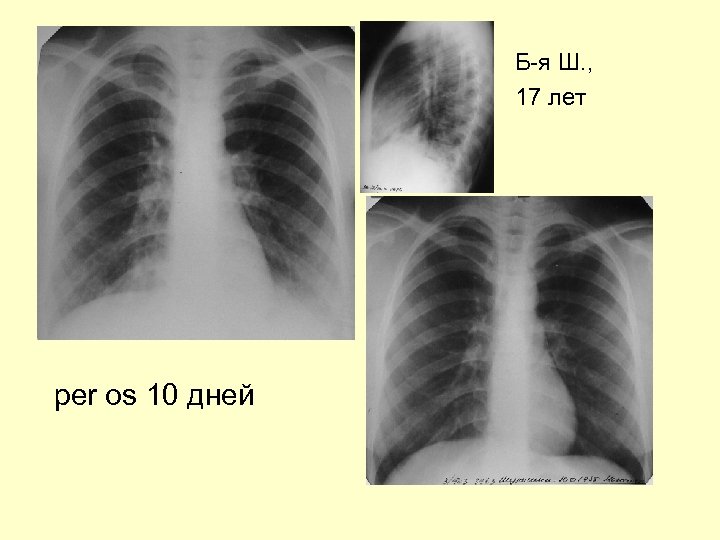

Рентгенограмма через 10 дней лечения макропеном

Рентгенограмма через 10 дней лечения

Б-я Ш. , 17 лет per os 10 дней

Динамика 10 дней